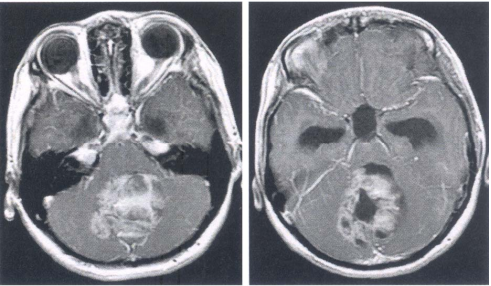

74 80 歲林先生,近來感覺疲倦、頭暈。家人說他瘦了,皮膚蒼白。血液檢查肝功能正常,進而為他做 鋇劑灌腸 X 光攝影檢查,影像如圖示。林先生最可能患了什麼病?

(A)潰瘍性大腸炎(ulcerative colitis) (B)結腸套疊(intussusception) (C)克隆氏疾症(Crohn’s disease) (D)結腸癌(colon cancer)